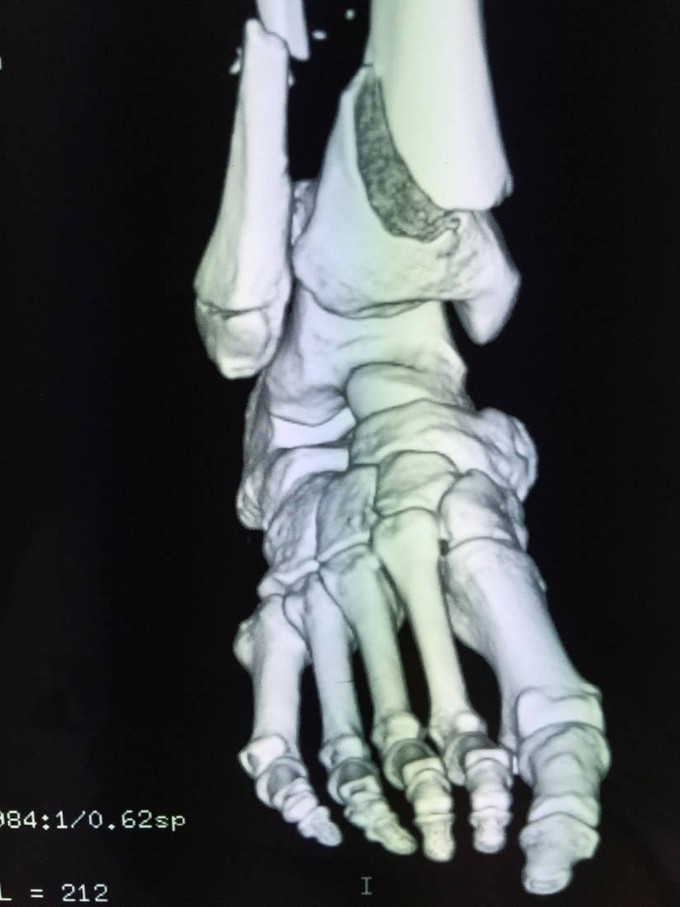

诊断:左胫腓骨远端开放性粉碎性骨折 患者车祸入院后行行抗炎消肿止疼等对症治疗后约一周,局部皮肤软组织条件差,局部皮肤全层坏死,行左胫腓骨远端外固定架固定术。

患者皮肤条件差,行外固定架维持患肢长度,如果直接行内固定治疗,切口处易感染,危险。